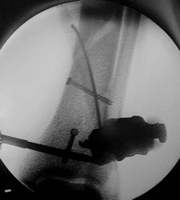

Röntgenkontrolle mit dem Bildwandler im OP

Achsengerechte Stellung der Fraktur